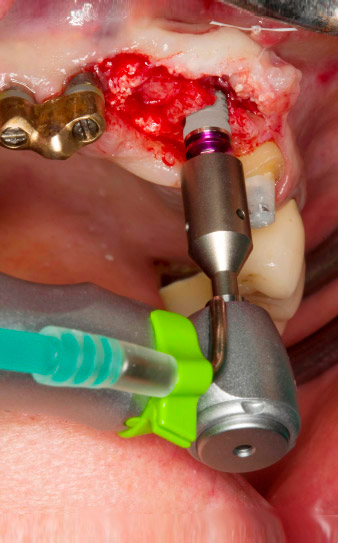

Tapping with the WS-75 L contra-angle handpiece

Fig. 3: Tapping with the WS-75 L contra-angle handpiece at a ratio of 20:1 (programme P4). Implantmed’s high torque, the hexagon chucking system for reliable power transmission and the automatic reversal of the direction of rotation when resistance gets too high prove particularly helpful here.